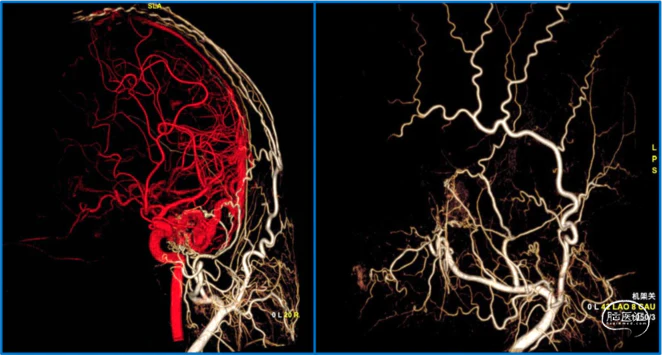

典型病例

蝶顶窦旁DAVF属于Borden III型,需要积极外科治疗。

蝶顶窦旁DAVF,可吸引前和中颅窝硬膜的所有动脉参与供血。其中颈内动脉及其分支的供血可以使用显微外科技术阻断;颈外动脉的供血动脉可以使用介入栓塞技术阻断。

介入栓塞眼动脉供血的要点:超选左侧眼动脉,跃过视网膜中央动脉,栓塞脑膜回返动脉对DAVF的供血。目的:保护眼动脉视网膜中央动脉分支,避免后期栓塞颈外动脉的供血动脉时损伤眼动脉。

引流静脉是否引流进入海绵窦,决定DAVF诊断为“颈动脉-海绵窦动静脉瘘”还是“蝶顶窦旁DAVF”。

静脉的引流路径决定患者静脉高压的临床表现,预后风险,治疗方案。

稳妥的外科治疗方案:先介入栓塞颈外动脉的供血动脉,然后显微手术切断颈内动脉的供血动脉,阻断引流静脉,电凝封闭硬膜瘘口。

神经内镜可以辅助确认颞极深部的引流静脉,避免残留引流静脉。